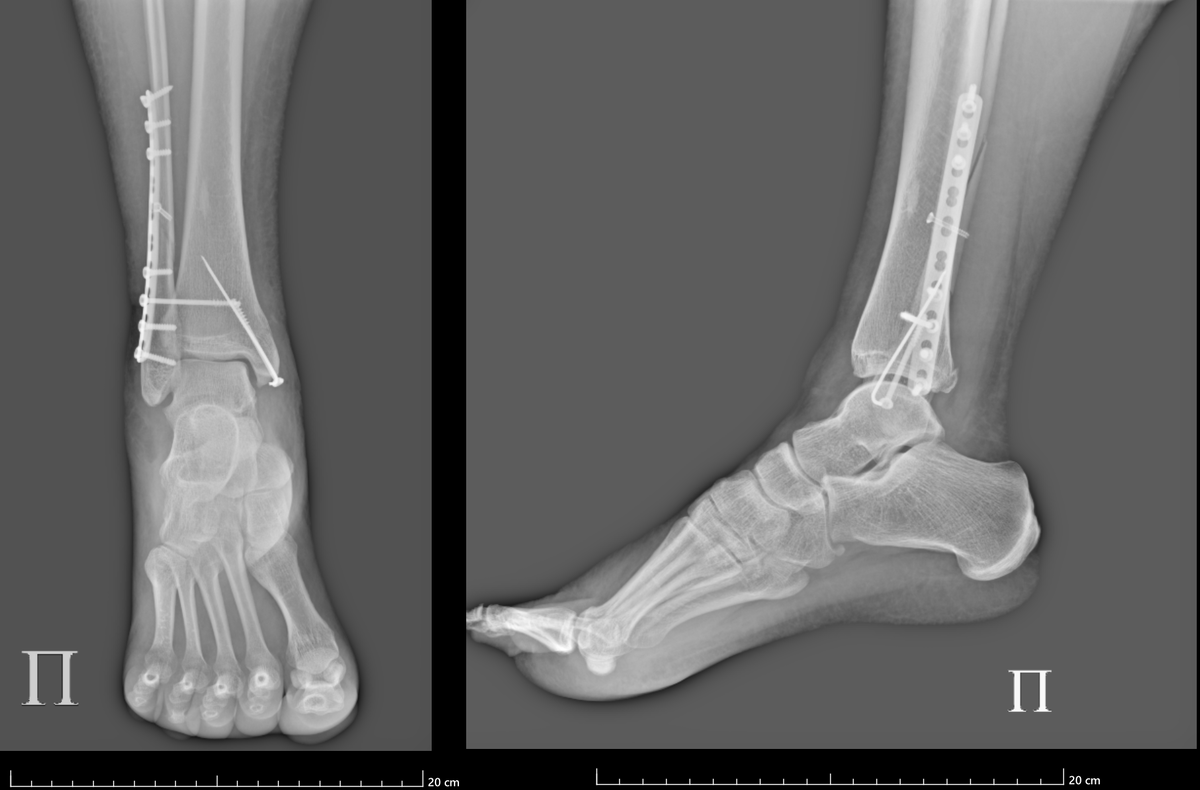

11 августа 2025 года я сломала ногу при самостоятельной посадке на параплане в Чегеме, 18 августа мне успешно собрали ногу обратно в Склифе. Прошло уже 2 месяца с операции, скоро уже будет вторая плановая операция. Пришло время поделиться тем, как у меня идут дела на реабилитации. И идут они хорошо. Если не читали предысторию, ссылки оставила в конце. Там всё: как сломала ногу, как местные СМИ всё переиначили на свой лад (и как всё было на самом деле), как мы выбивали у АльфаСтрахования трансфер из Нальчика в Москву – короче, рекомендую потом почитать. Для меня опыт подобной иммобилизации и такого серьезного перелома был первый (и надеюсь, что последний). До этого все приключения обычно заканчивались очередным шрамом, ушибом, синяком, ссадиной. Руку ломала всего 2 раза, так что тут мне хвастаться нечем. А тут я познакомилась со новыми прелестями жизни: отекшая нога, сложности в самообслуживании, бессонные ночи из-за болей, бытовая недееспособность — короче, ставлю этому опыту ноль из д

11 августа 2025 года я сломала ногу при самостоятельной посадке на параплане в Чегеме, 18 августа мне успешно собрали ногу обратно в Склифе. Прошло уже 2 месяца с операции, скоро уже будет вторая плановая операция.

Сейчас готовлюсь к удалению позиционного винта, потому что уже пора. Анализы сдала, жду подтверждение даты операции.

По словам врача — это приключение на 20 минут: ногу обезболят, надрез маленький сделают, отверткой специальной выкрутят, зашьют.

Затем мне ещё какое-то время носить остальные железки, которые потом надо будет вытащить. И судя по озвученным прогнозам, носить мне это ещё минимум полгода.